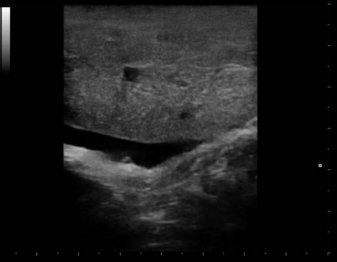

Eight intact female cats were referred for the treatment of FAC between 2015 and 2020. Ages at admission ranged from 8 to 12 months (Table 1). Four cats were domestic shorthair (C1, C2, C5, and C8), two cats were Maine Coon (C3 and C6), and two were Persian (C4 and C7). None of the cats received exogenous progestins but had a history of recent heats. Four cats (C5, C6, C7, and C8) had been mated and were between the 25th and 32nd day of pregnancy at presentation. The mammary glands were bilaterally enlarged, and no milk secretion was detected. Skin ulceration, inflamed, and painful mammary glands were present in six cases (C1, C2, C3, C5, C7, and C8) (Fig. 1a and b). General signs (tachycardia, lethargy, and anorexia) were strongly related to these changes. The diagnosis of FAC was based on clinical symptoms. Fine-needle aspiration biopsy of the mammary tissue was performed to support the clinical diagnosis. The combination of glandular-epithelial tissue and mesenchymal cells and the absence of prevalent immune cell populations in the cytologic smears allowed to exclude malignant growth or mastitis. Ultrasound examination of the mammary gland and doppler was employed to evaluate the structure and vascularization of the enlarged gland. FAC presented mainly as a well-circumscribed solid mass of granular, slightly hyperechoic texture, with regularly delimited margins. There was a uniform distribution of vascularity. Anechoic areas were present in the parenchyma and outside the margins (Fig. 2). Owners gave their consent to conservative treatment to preserve fertility and the integrity of the mammary glands. Mastectomy was not performed in any cases. Non-pregnant cats (C1, C2, C3, and C4) were treated on two consecutive days with subcutaneous injections of 15 mg/kg Aglepristone (ALIZIN; Virbac, Carros, France). The treatment was continued weekly with a single injection until the resolution of signs. If signs of ulcers, inflammation, or necrosis were evident in at least one mammary gland, 12.5 mg/kg q 12 hours of amoxicillin / clavulanic acid tablet formulation (SYNULOX; Zoetis, Rome, Italy) and 0.1 mg/kg q 24 hours of meloxicam (MELOXORAL oral suspension 0,5/ml; Dechra Veterinary Products, Turin, Italy) for the first day, followed to 0.05 mg/kg q 24 hours was given for 5–6 days. Furthermore, an oral dietary supplement containing maltodextrin and bromelain (BROSPET; Aurora biofarma, Milan, Italy) was administered once a day for the treatment period. Ulcers were treated topically twice daily with a cream containing hypericum and neem extract (HYPERMIX; Rimos, Mirandola, MO, Italy). The enlarged mammary glands were daily massaged with an emollient gel based on Aloe vera (ALOPET GEL; linea Angel Ariel, Grancona, VI, Italy). Two of the four pregnant female cats were treated with the same schedule for the severe enlargement and ulceration of the mammary glands (C5) and early signs of fetal resorption, deduced by the slow heart rate and the increased echodensity of amniotic fluid (C6). After 1 week, they presented bloody vaginal discharge, and ultrasound revealed four placental remnants in a cat (C6) (Fig. 3). Cloprostenol (ESTRUMATE; MSD Animal Health, Segrate, MI, Italy) at the dosage of 1.5 mcg/kg was given for three consecutive days to facilitate uterine emptying. Two pregnant female cats (C7 and C8) were treated with the schedule less the aglepristone drug to preserve the litters. In all the cases studied, after 2–3 weeks, the mammary gland reduced in size, and no ulcers or necrotic areas were detected, and after 4–5 weeks, the lesion was not more recognizable. At term, pregnant queens C7 and C8 delivered four and three kittens, which were normally nursed and weaned after 40 days (Fig. 1c). The case series is summarized in Table 1. A 1-year follow-up reveals no recrudescences of FAC in treated animals.

Fig. 3. Case C6. A pregnant 1-years-old Maine Coon cat with FAC presenting placental remnants at ultrasound after the treatment with aglepristone.